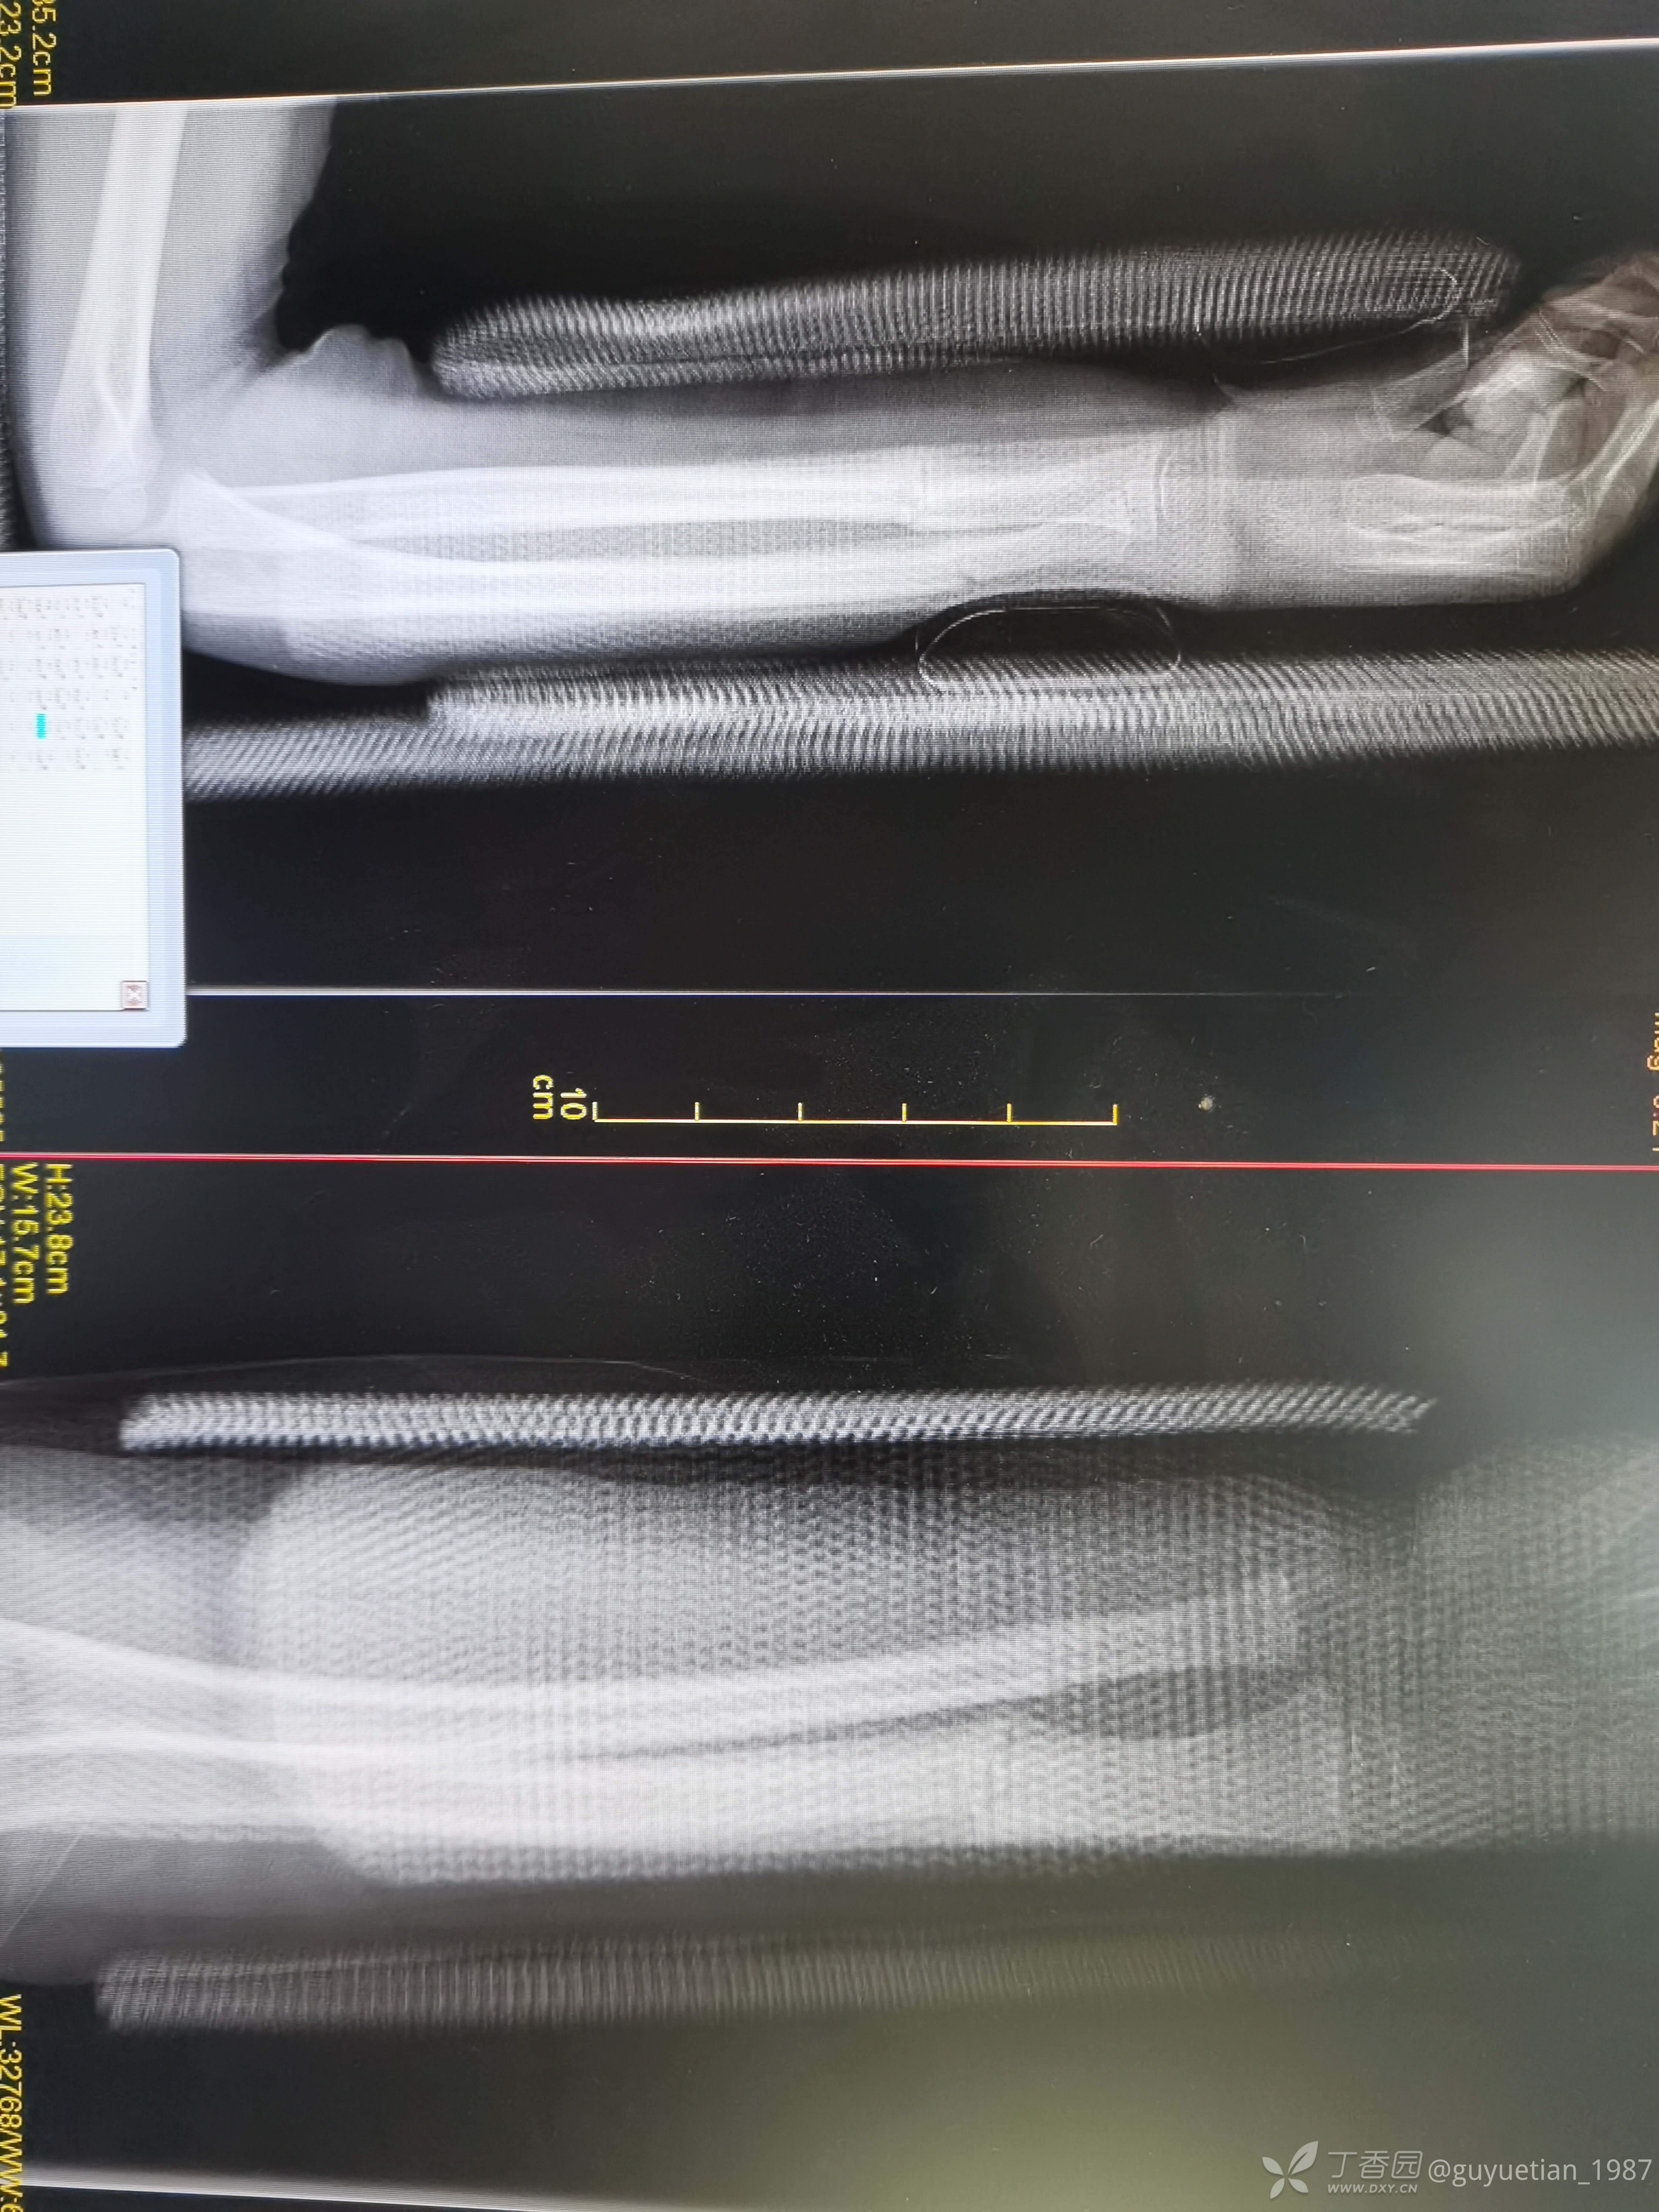

果然儿童前臂骨折很容易发生二次骨折。夜急诊来院,尺桡骨中远1/3双骨折。即刻复位,自制小夹板旋后位固定,复位并不理想,与家属沟通病情(手术与保守的利弊),家属充分理解后选择保守治疗。

然后就是一周后复诊,侧位像背侧成角。门诊医生斩钉截铁告知这样的位置必须要手术治疗。犹豫后又电话联系再次找到我,再次纠正力线,背侧加了块压垫。复片后力线还行,但是感觉到家属开始犹豫了(门诊是一位资深老医生,专做保守,当地小有名气,说话当然比我有分量),再次坐下来跟爸爸沟通病情,还是让他自己做出选择,手术还是保守?利弊让他自己权衡,当然个人还是希望他保守,对于这个年龄孩子能不手术尽量不要手术(心底知道保守肯定没有问题),适时掏出手机给他看了曹老师的保守治疗典型病例给家属来颗定心丸。